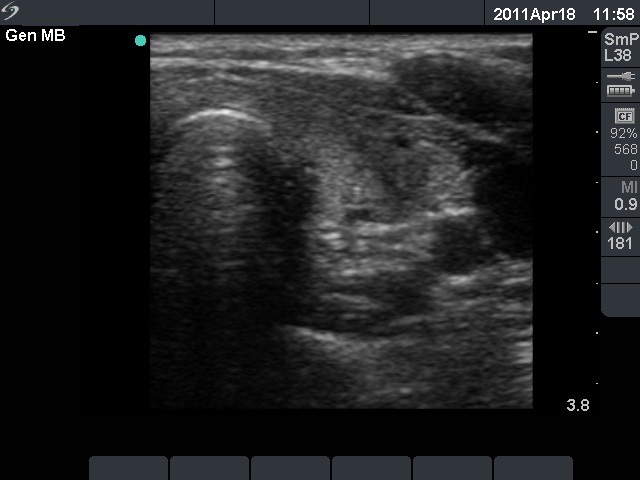

Ultrasonography: The right thyroid was echonormal and contained several small, insignificant lesions. There was a hypoechogenic lesion with blurred borders in the central and in the ventro-medial part of the left thyroid with increased intranodular blood flow.

The ultrasound pattern of de Quervain's thyroiditis and that of papillary cancer are very similar: a hypoechogenic lesion with blurred borders are found in both cases. They differ in vascularization statistically but the vascular pattern has only limited practical significance. In the acute phase of de Quervain's thyroiditis the vascularization is generally decreased but even in this case the situation was the opposite. The finding of not one but multiple hypoechogenic areas favored the possibility of subacute thyroiditis.